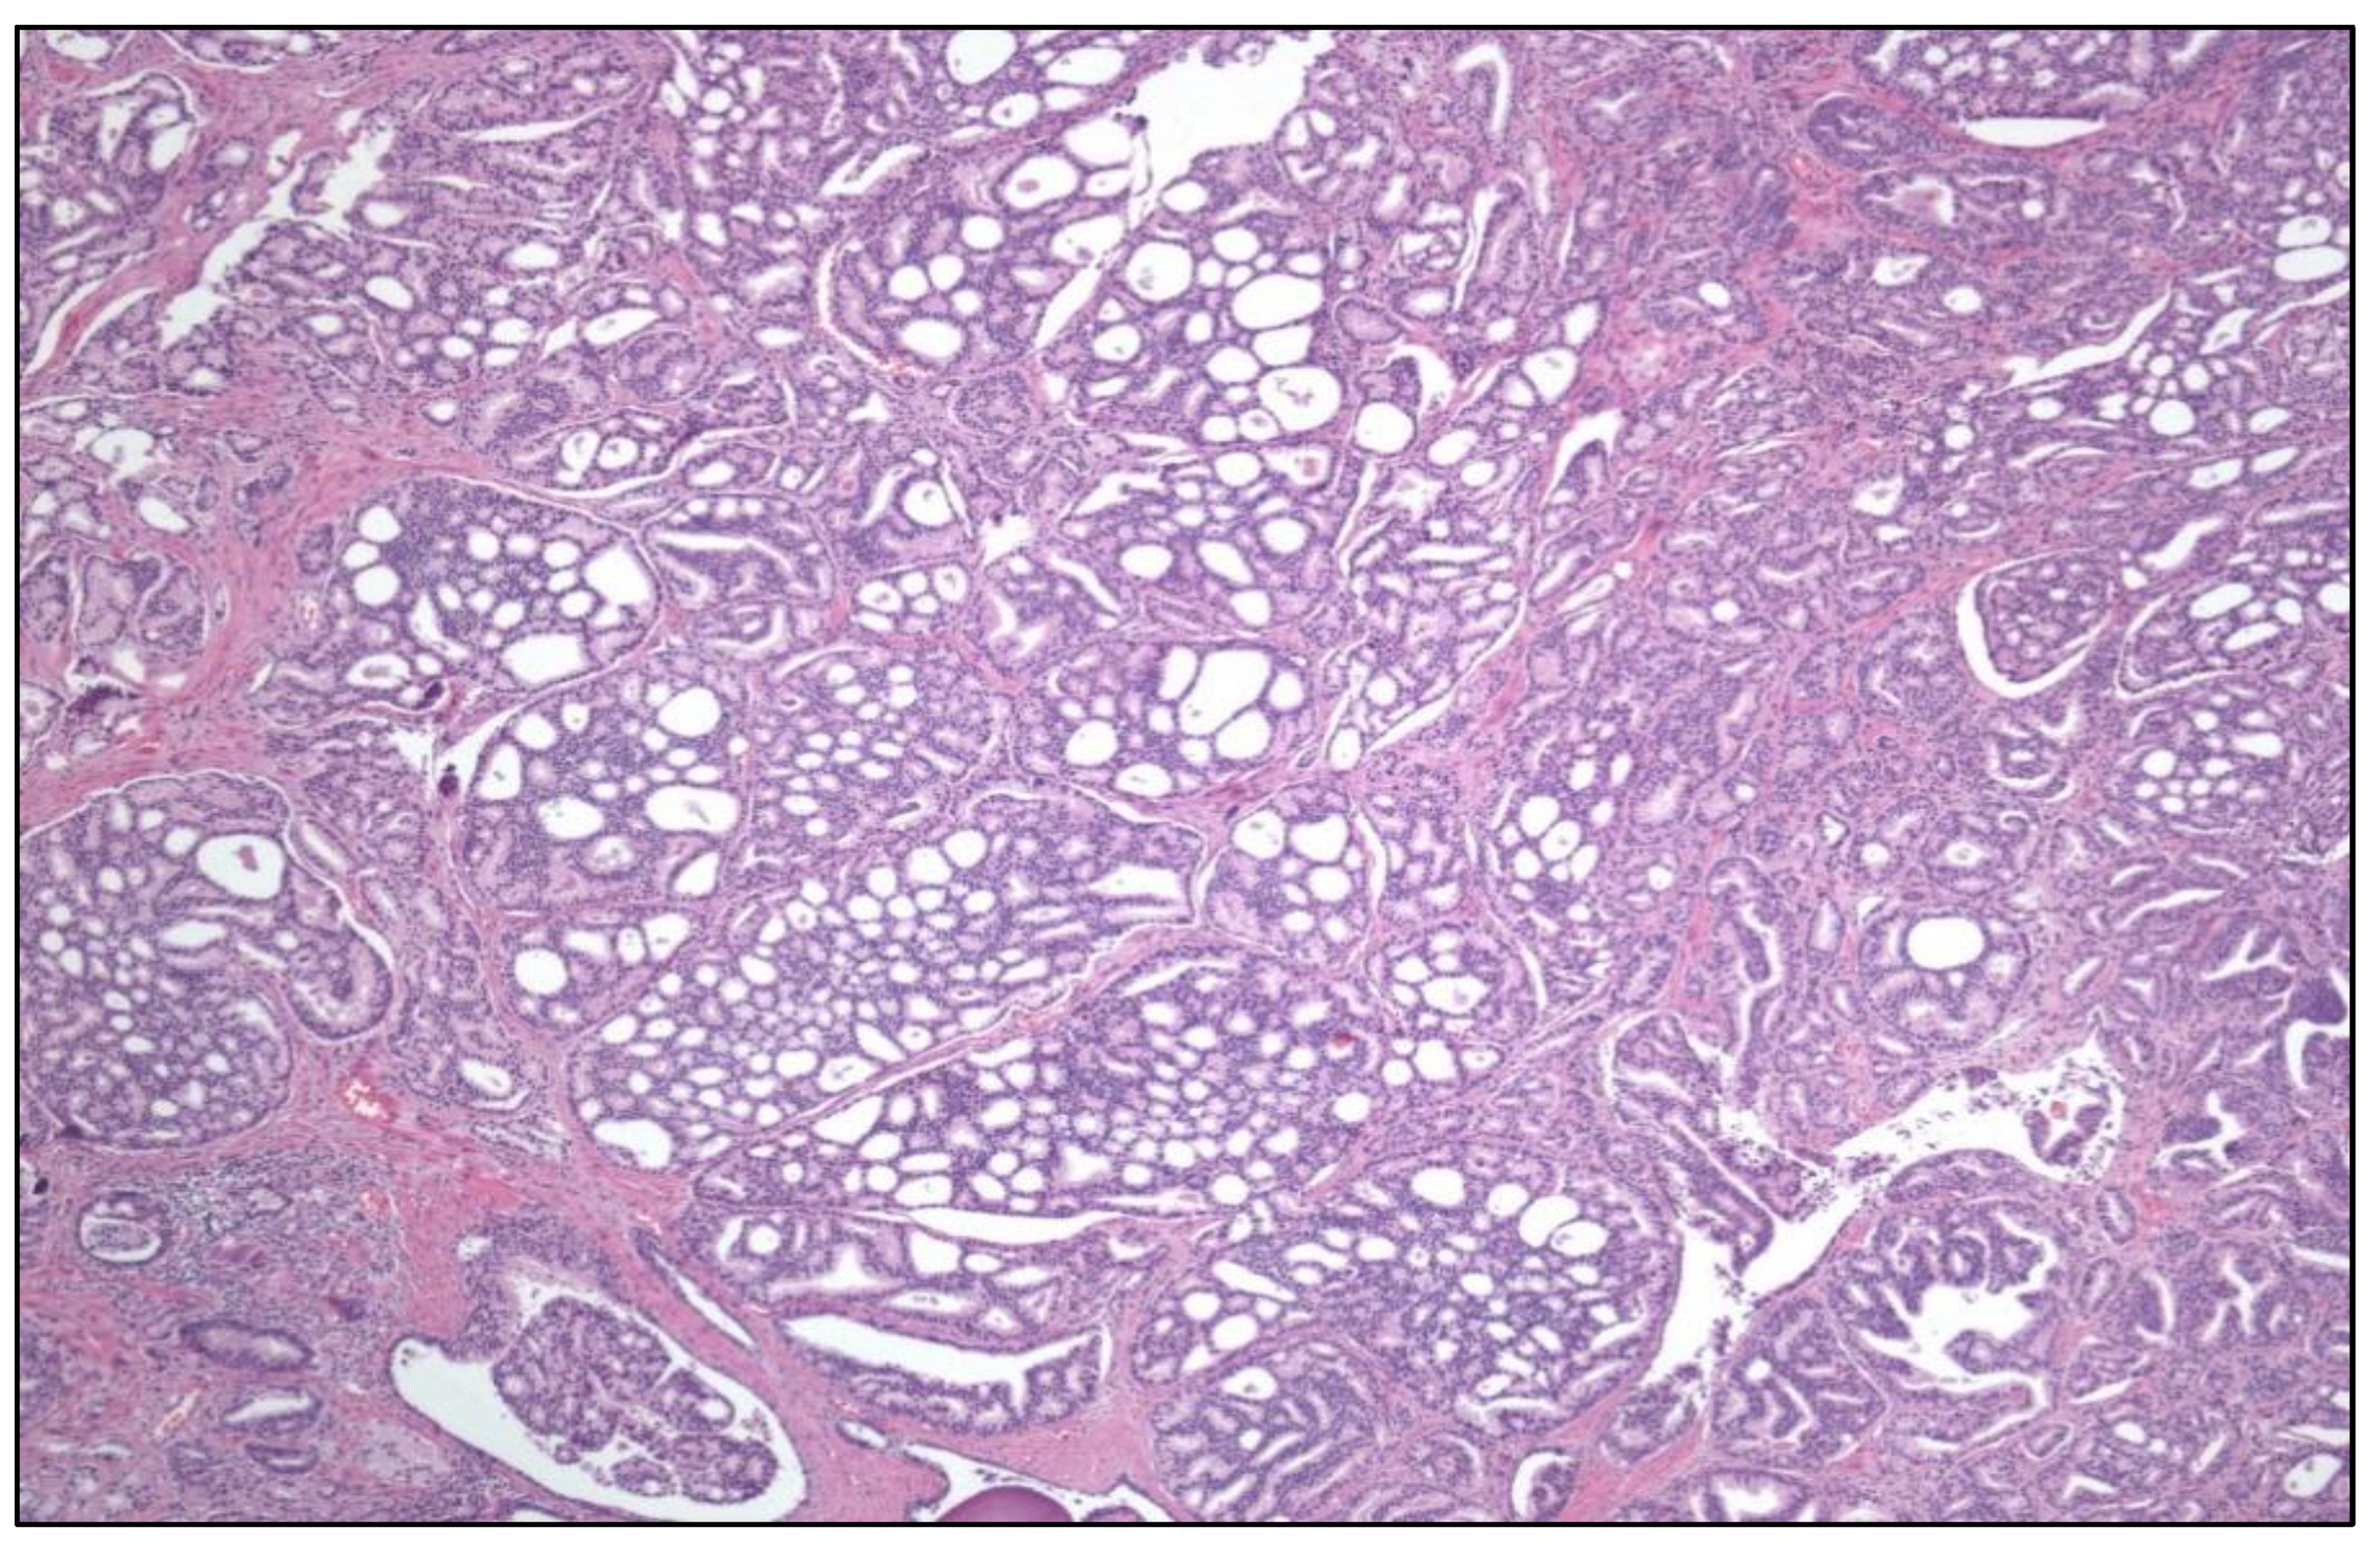

New renal tumor entities have been included in the long list of RCC [4], i.e., eosinophilic solid and cystic RCC (ESC RCC) (Figure 2), ELOC-mutated RCC, ALK-rearranged RCC, SMARCB1-deficient medullary RCC, TFEB-altered RCC, and FH-deficient RCC.

Papillary RCC (PRCC) classification has been fully rearranged. The formerly called PRCC type 1 is not a unique entity and includes several new variants, i.e., renal neoplasm with inverted polarity (mutated in KRAS), psammomatous hyalinizing RCC (mutated in NF2), biphasic alveolo-squamoid renal RCC, and thyroid-like follicular RCC (EWSR1-PATZ1 fusion). On the other hand, the “old” PRCC type 2 is no longer a specific entity and has been broken down into several new ones, i.e., FH-deficient RCC, tubulo-cystic RCC, eosinophilic solid and cystic RCC (ESC RCC), SMARCB1-deficient medullary RCC, and RCC of the MiTF group.

RCC is becoming in the last decade a neoplasm with an increasingly complex constellation of clinical, histological, and molecular features conforming one of the hottest and exciting topics in Pathology. In this particular context, the Genitourinary Pathology Society (GUPS) has brought order to this puzzle updating in 2021 the last findings in existing WHO RCC [6] as well as an update of the list of renal tumor novelties [7]. New tumors includes novel [eosinophilic solid and cystic RCC, ALK rearrangement-associated RCC, and RCC with fibromyomatous stroma (Figure 6)], emerging (eosinophilic vacuolated tumor and thyroid-like follicular RCC), and provisional (low-grade oncocytic tumor, atrophic kidney-like lesion, and biphasic hyalinizing psammomatous RCC) tumor entities. A detailed compiled description with a literature review of all these tumors is provided in the aforementioned GUPS article [7].

Figure 2. Eosinophilic solid and cystic renal cell carcinoma with its characteristic CK20 positivity (right).